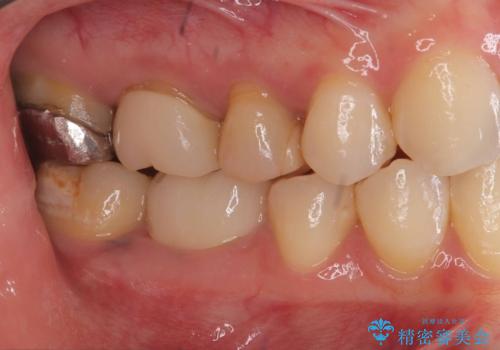

- 「銀歯を白くしたい」が主訴の患者様です。

銀歯を除去後、オールセラミッククラウンで治療を行いました。

被せ物のやり変えのみ希望だったため、根管とコアはさわっていません。

銀歯と虫歯を除去後、オールセラミッククラウンで治療を行いました。